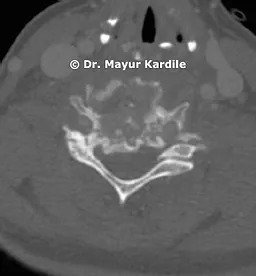

CT scan of the cervical spine revealed complete destruction and collapse of C5 and C6 vertebra with kyphosis deformity